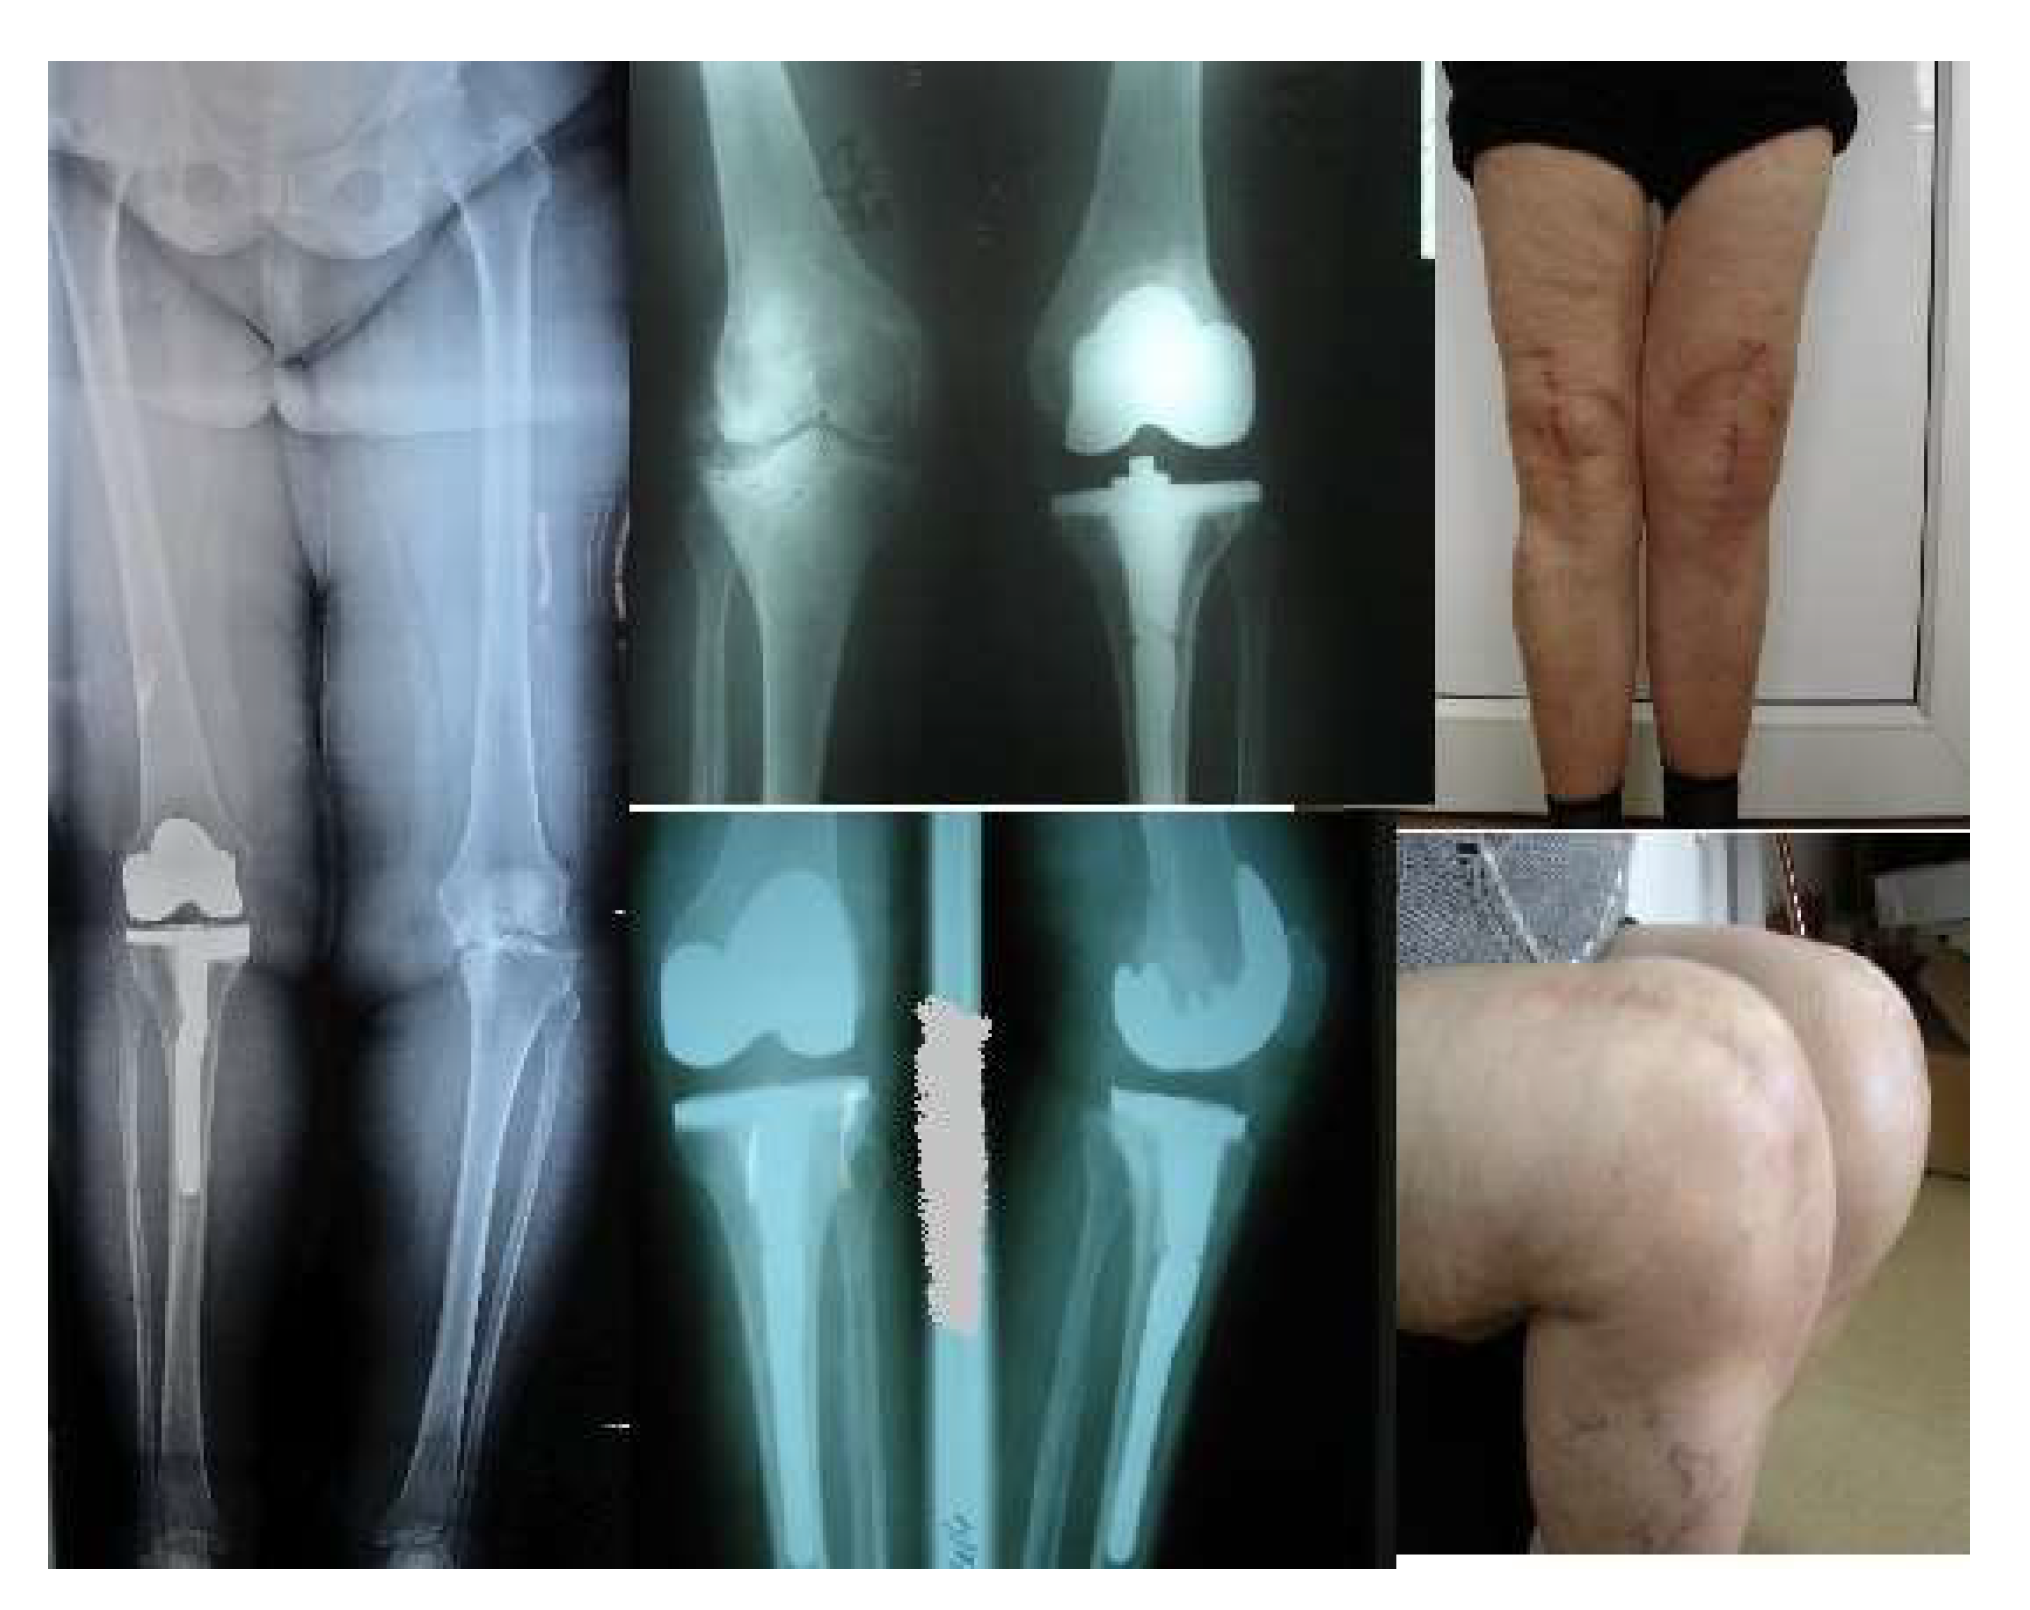

Since 2017, we have used this modified method on 706 TKA patients, including 302 females and 281 males. Their ages ranged from 45 to 78. Eighty of those 706 TKA cases had severe deformities, such as large preexisting defects, osteoporotic bone structure, or severe varus-valgus deviation. A tibial stem extension was added to the regular prosthesis to dissipate the stress levels, reducing the risk of failure in severe knee deformity.

Only 38 out of 80 tibial stem extension in primary TKA, had varus deformity, more than 15°, 25 had valgus deformity, 10 had severe osteoporosis, 4 rheumatoid arthritis with osteoporotic bone structure and 3 had previous proximal correction osteotomy or callus deformity. The same type of implants was used with or without tibial stem extension. Stem lengths varied from 80 mm to 140 mm.

Eighty of those 706 TKA cases had severe deformities, such as large preexisting defects, osteoporotic bone structure, or severe varus-valgus deviation. The same type of implants was used with or without tibial stem extension. Stem lengths varied from 80 mm to 140 mm.

Eighty of those 706 TKA cases had severe deformities, such as large preexisting defects, osteoporotic bone structure, or severe varus-valgus deviation. This modified approach permit us to correct also these severe diformities. The same type of implants was used with or without tibial stem extension. Stem lengths varied from 80 mm to 140 mm.

Radiographic evaluation reported 2 cases of tibial implant loosening in the lot with standard components. The average pain and function scores at the time of assessment were 85 and 83. Average range of motion was 110° at the latest follow-up, respectively. Kaplan-Meier survivorship was 98.6% at 7 years. No significant difference in VAS score, WOMAC, FJS, or OKS.

The preoperative planning is mandatory, but the final decision will be intraoperatively whether to use tibial stem extension or not in total knee arthroplasties with severe deformity. Tibial stem extension must be used in osteoporotic or large preexisting bone defects in severe varus-valgus deformities. The stem length and diameter must be precisely chosen carefully to diminish the failure rates. The clinical results support the use of stems in difficult primary total knee arthroplasties. To determine the diameter and length of the components' extensions that are most suited for the patient, more research might be needed in the future.

Preoperative planning is mandatory, but the final decision will be intraoperative to use or not use tibial stem extension in total knee arthroplasties with severe deformities. This modified approach is useful even in severe knee deformity allowing tibial stem extension. Tibial stem extension is recommended for severe deformities, osteoporotic conditions, and large pre-existing bone defects. The diameter and length of the stem must be selected to reduce the failure rate. The stem length and diameter must be precisely chosen carefully to diminish the failure rates. The clinical findings lend credence to using stems in challenging primary total knee replacements.